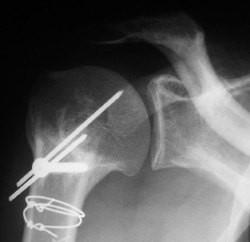

POST-OPERATORIO

POST – OPERATORIO